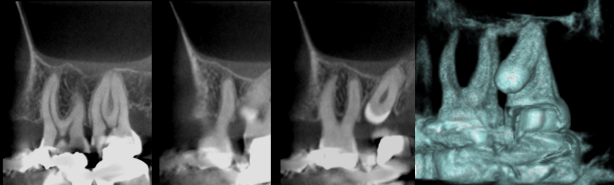

- Tac 3D (Tecnologia Cone Beam 3D)

- Radiografie endo-orali